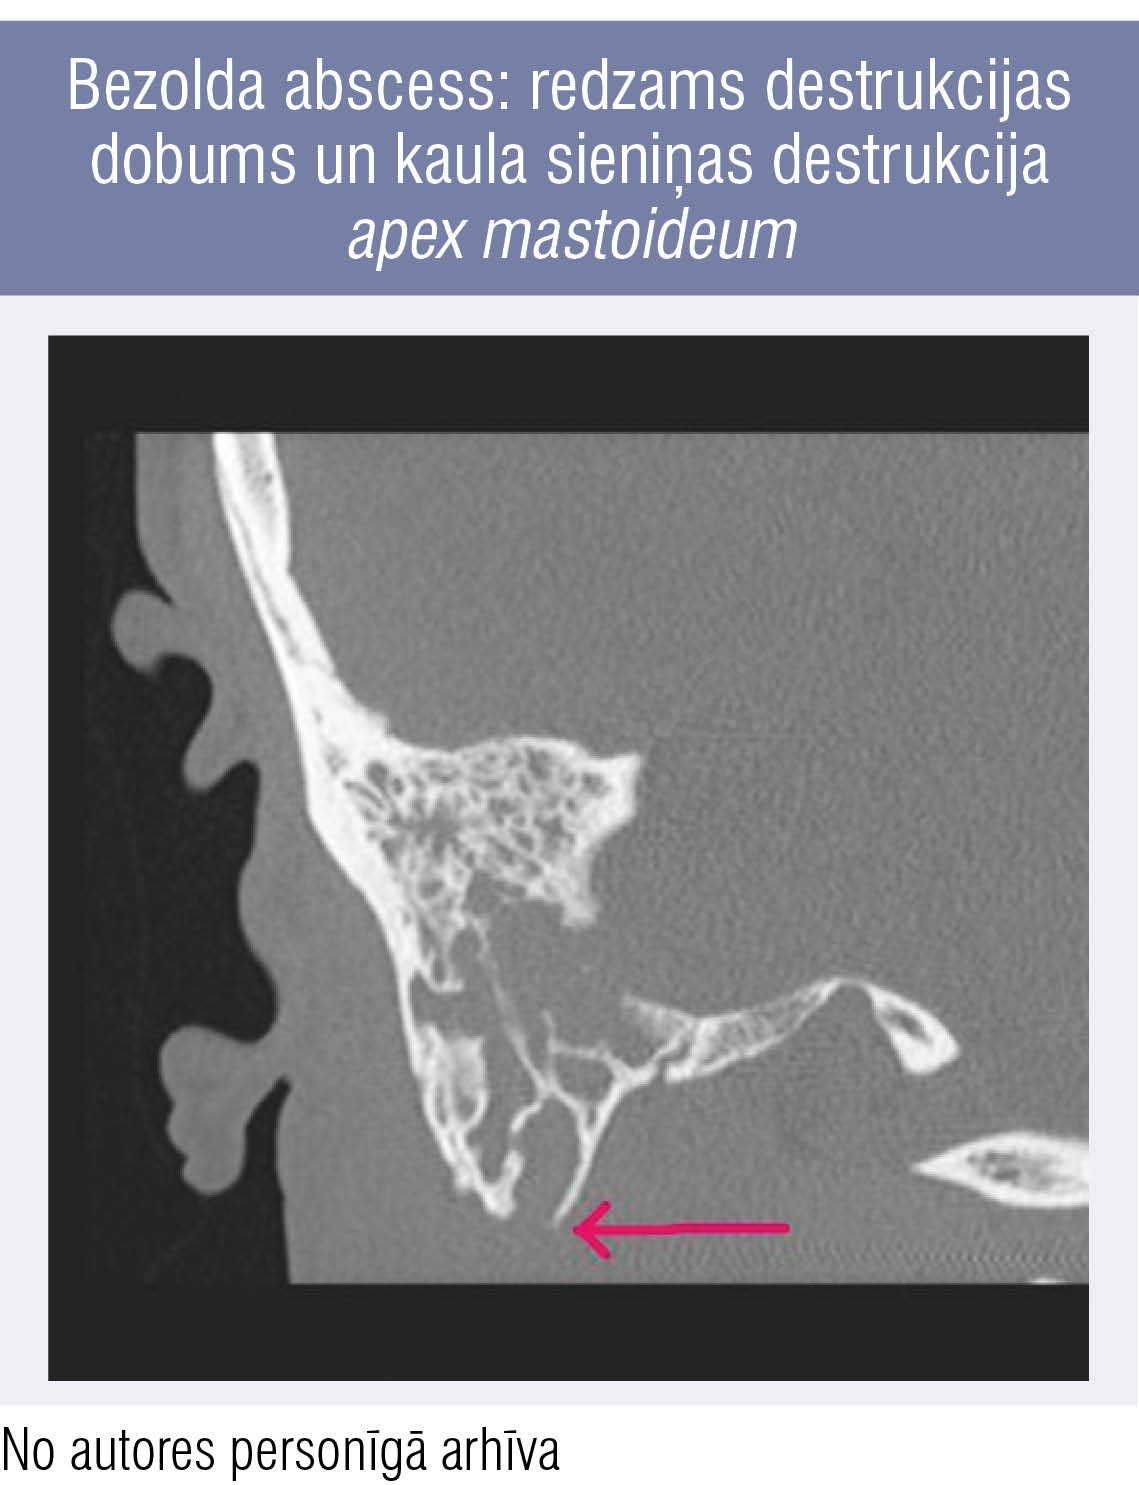

Bezolda abscess: redzams destrukcijas dobums un kaula sieniņas destrukcija apex mastoideum Bezolda abscess: redzams destrukcijas dobums un kaula sieniņas destrukcija apex mastoideum

2. attēls

Bezolda abscess: redzams destrukcijas dobums un kaula sieniņas destrukcija apex mastoideum

Diagnozes apstiprināšanai nepieciešama deniņkaula piramīdu datortomogrāfija (1. attēls). Mastoidīta gadījumā tur redzama aizauss kaula šūnu sieniņu destrukcija, destrukcijas dobuma veidošanās. Kaula destrukcija uz planum mastoideum pusi var veidot subperiostālu abscesu. Ja destrukcija un abscess izveidojas apex mastoideum apvidū, tad strutas tālāk var slīdēt uz leju gar m. sternocleidomastoideus uz kakla apvidu un dziļajām kakla starpfasciju telpām (Bezolda abscess, 2. attēls).